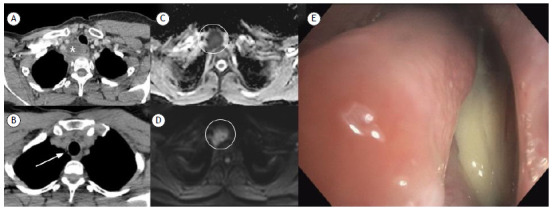

Complicated tracheal diverticulitis.